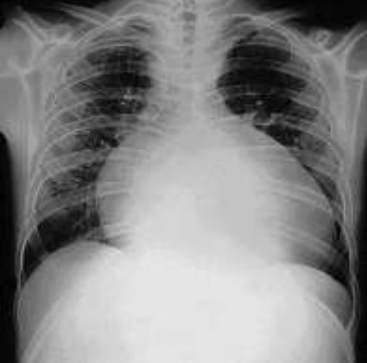

Lactente de 6 meses, previamente hígido, é levado à emergência pediátrica com quadro de tosse produtiva há 2 dias, associado com febre de 39 graus e dispneia. Ao exame físico: regular estado geral, descorado 1+, hidratado, acianótico, anictérico e afebril. FC = 180 bpm, FR = 65 ipm, SatO2 95% em ar ambiente. Murmúrio vesicular normodistribuído, com estertores subcrepitantes difusos, com tiragem subcostal moderada, 2 bulhas rítmicas hipofonéticas, sem sopros cardíacos. Pulsos periféricos cheios e TEC 4 segundos. Abdome com fígado palpável a 4 cm abaixo do rebordo costal direito. Restante sem alterações. Foi solicitado Rx tórax

(vide abaixo – fonte: Medscape®).